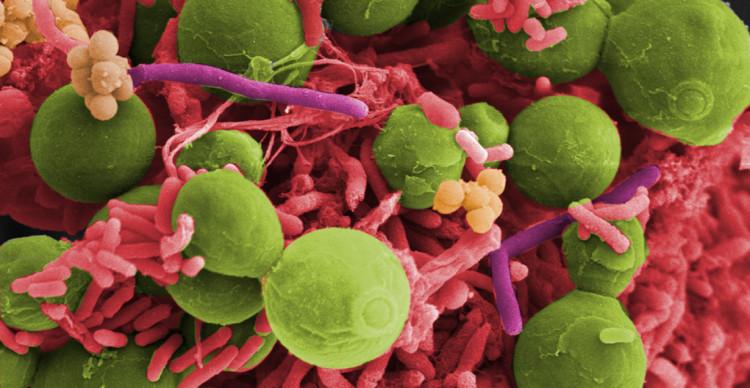

Center for Advanced Biomaterials for Health Care

Interdisciplinary Research Centre on Biomaterials (CRIB), Naples

The Center for Advanced Biomaterials for Health Care (CABHC) develops materials and technologies to engineer bio-logically inspired platforms and systems for applications in the biomedical sector.